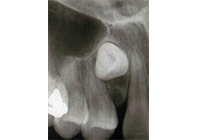

上顎犬齒是牙齒萌發順序最晚的牙齒,加上它萌發的路徑較其他牙齒長,這也造成上顎犬齒是上顎最常見的阻生牙。女性的好發率也高於男性。上顎機率高於下顎。診斷出上顎犬齒阻生需要靠臨床觀察與影像學判斷。在影像學方面,根尖片雖然是一個二維的影像,但是可以顯示牙齒與鄰牙間的相對關係。而確切的位置評估則需要藉由電腦斷層來定位。如果較晚發現犬齒已異位萌發,則可以藉助翻辫瓣手術將矯正器黏在犬齒,並用矯正力量拉下犬齒。 (圖05-08)

圖5

圖6

圖7

圖8

參考病例: 阻生齒露出-上顎犬齒